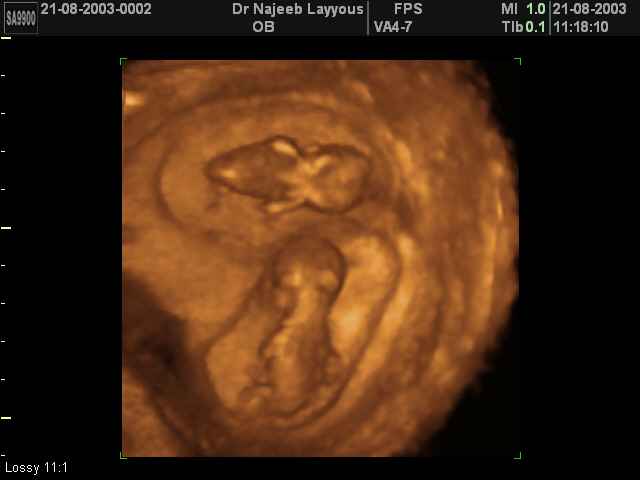

- 3D Photos échographie de grossesse multiple